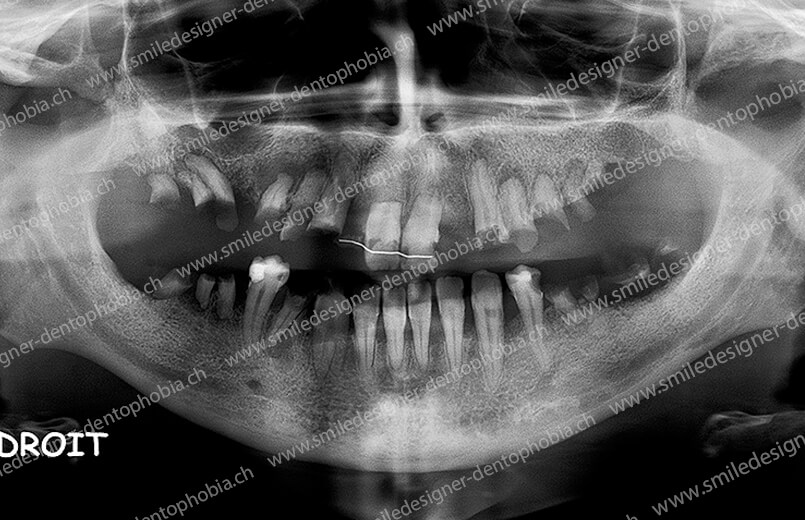

Cas clinique « DOMINO SURGERIES MCI » : Bridge implanto-porté sans extension postérieure (ALL ON 10/8). Version définitive des bridges avec un cosmétique en céramique. Double comblements de sinus et double greffes osseuses d’apposition pour la reconstruction du maxillaire.

Cas clinique « DOMINO SURGERIES MCI » : Bridge implanto-porté sans extension postérieure (ALL ON 8/6). Version définitive des bridges avec un cosmétique en céramique. Double comblements de sinus et double greffes osseuses d’apposition pour la reconstruction du maxillaire.

Cas clinique « DOMINO SURGERIES MCI » : Bridge implanto-porté avec extensions postérieures (ALL ON 6/6).

- Résorption osseuse avancée (notamment au niveau des sinus maxillaires).

- Dents manquantes ou condamnées en raison de pathologies (parodontite, kystes, etc.).